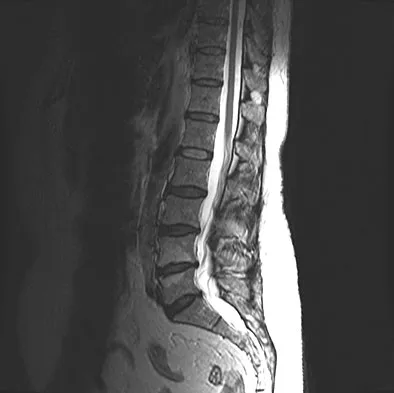

Prepare for AAOS & ABOS boards with Orthopedic MCQs (Set 1). This comprehensive review covers high-yield ques…

Master AAOS & ABOS with practice MCQs for Set 1, covering complex spine disorders, sports medicine injuries, …